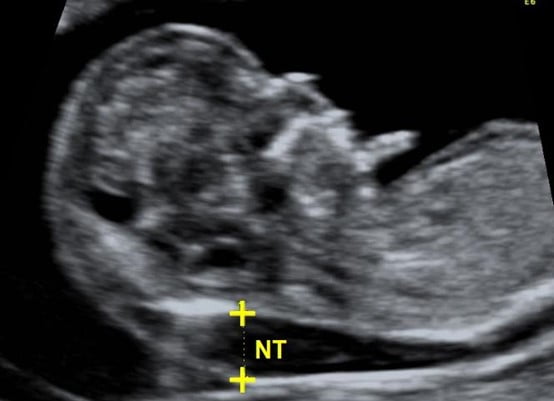

Με τον όρο «αυχενική διαφάνεια», εννοούμε την υπερηχογραφική εξέταση, που πραγματοποιείται στο τέλος του πρώτου τριμήνου της κύησης και η οποία βοηθά να προσδιοριστεί, εάν ένα μωρό είναι στατιστικά πιο πιθανό να πάσχει από κάποια χρωμοσωμική ανωμαλία, με συνηθέστερη την τρισωμία 21 (σύνδρομο DOWN).

Η εξέταση της αυχενικής διαφάνειας, επικεντρώνεται στο πίσω μέρος του αυχένα του εμβρύου, όπου σε αυτό το σημείο τείνει να συσσωρεύεται υγρό, σε έμβρυα με χρωμοσωμικές ανωμαλίες.

Ποια είναι μια φυσιολογική τιμή κατά τη μέτρηση της αυχενικής διαφάνειας;

Οι φυσιολογικές τιμές στις οποίες κυμαίνεται η αυχενική διαφάνεια ποικίλλουν και εξαρτώνται από την εβδομάδα κύησης, στην οποία βρίσκεται η γυναίκα. Σε γενικές γραμμές πάντως, θα λέγαμε πως οι περισσότεροι ιατροί θεωρούν ότι μια φυσιολογική μέση τιμή στις 12 εβδομάδες, είναι κάτω από 2,5 mm.

Ο έλεγχος της αυχενικής διαφάνειας, κανονικά θα πρέπει να πραγματοποιείται μεταξύ της 11ης και της 13ης εβδομάδας της εγκυμοσύνης. Ο λόγος είναι πως μετά από αυτό το διάστημα, ο ιστός γίνεται παχύτερος και δεν είναι πλέον ημιδιαφανής, επομένως τα αποτελέσματα των δοκιμών καθίστανται ασαφή.